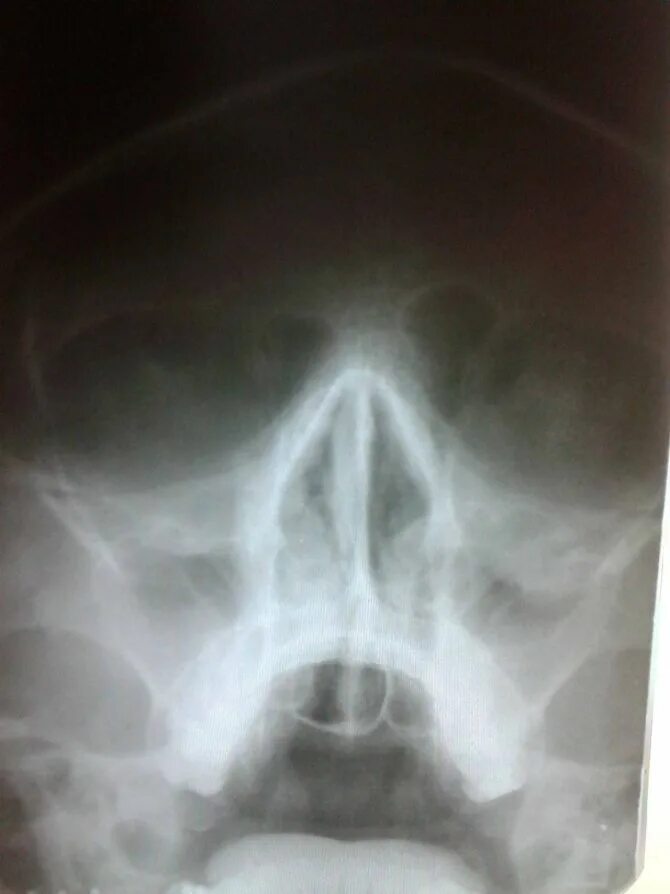

Гайморит сам проходит